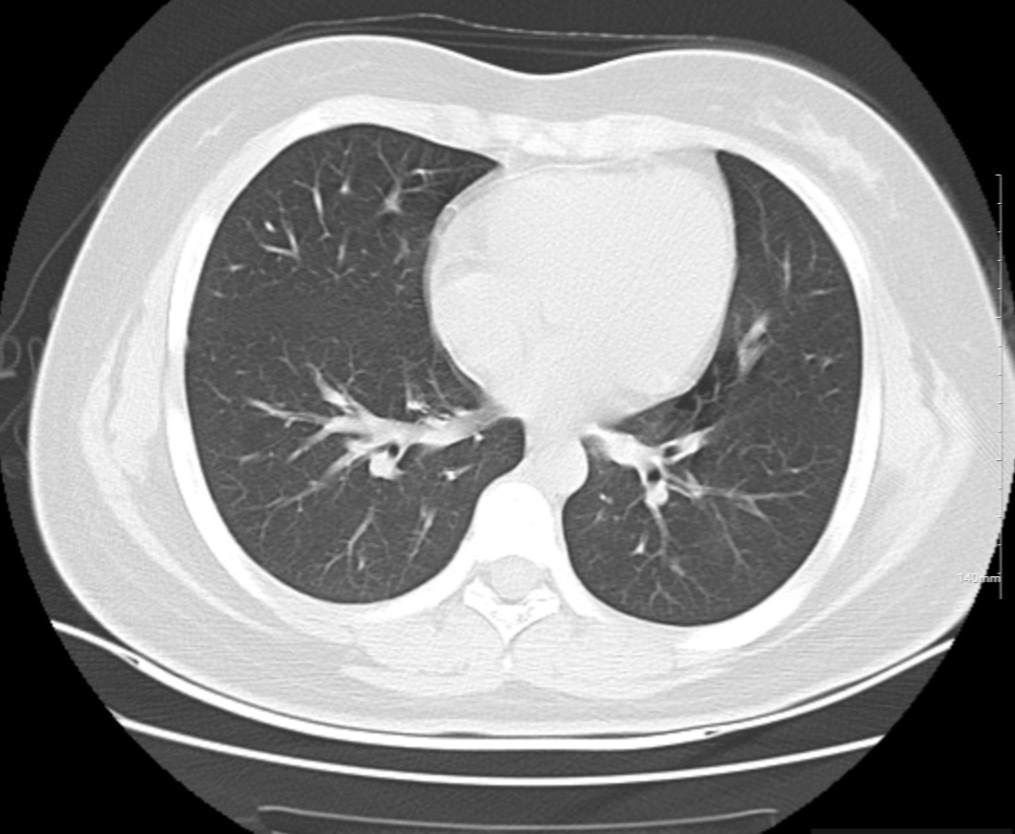

肺部CT:

支气管血管束增粗且伴 < 2 个肺叶的磨玻璃密度影, 多提示为单纯性百日咳肺炎。(下图:支气管血管束增粗, 两肺下叶基底段少许磨玻璃密度影)

如出现肺内支气管血管束增粗, 伴≥3 个肺叶斑片影、亚段性实变及支气管气象时, 提示患儿病情较重,可能合并其他感染。